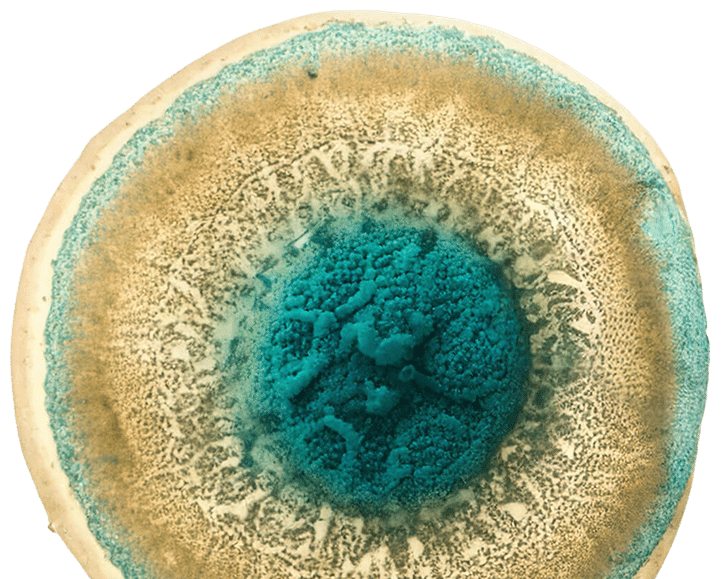

Muse cells (Multilineage-Differentiating Stress-Enduring cells) were discovered by Professor Mari Dezawa in Japan as rare endogenous cells with pluripotent-like behaviour, stress endurance and homing to damaged tissue. Over more than a decade, this discovery was translated into clinical-grade products: Dezawa MuseCells® (allogeneic IV Muse cell therapy) and Dezawa MuseExosomes® (Muse-derived, cell-free exosomes).

• Pluripotent-like: differentiation from single cells into derivatives of three germ layers.

• Stress-enduring and damage-sensing: survive stress, home to injured tissue. Non-tumorigenic in preclinical models (low telomerase, no teratoma formation).

• Pluripotent-like: differentiation from single cells into derivatives of three germ layers.

• Stress-enduring and damage-sensing: survive stress, home to injured tissue. Non-tumorigenic in preclinical models (low telomerase, no teratoma formation).

Muse cells demonstrate pluripotent-like differentiation from single cells and can integrate structurally into damaged tissue in models.